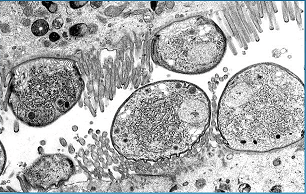

Kriptosporidiozu kod mačaka uzrokuju protozojski paraziti iz klase kokcidija Cryptosporidium Parvum i Cryptosporidium Muris. Cryptosporidium je široko rasprostranjen zbog milijuna cista koje bolesna životinja ispušta u vanjski okoliš s izmetom.

Cryptosporidium Parvum je lokaliziran u tankom crijevu i respiratornom traktu, gdje se razvija u epitelnim stanicama, kod životinja sa značajno smanjenim imunitetom i širi se na cijeli probavni trakt. Cryptosporidium Muris je lokaliziran na sluznici želuca i gotovo je jedini parazit koji živi u želucu mačaka.